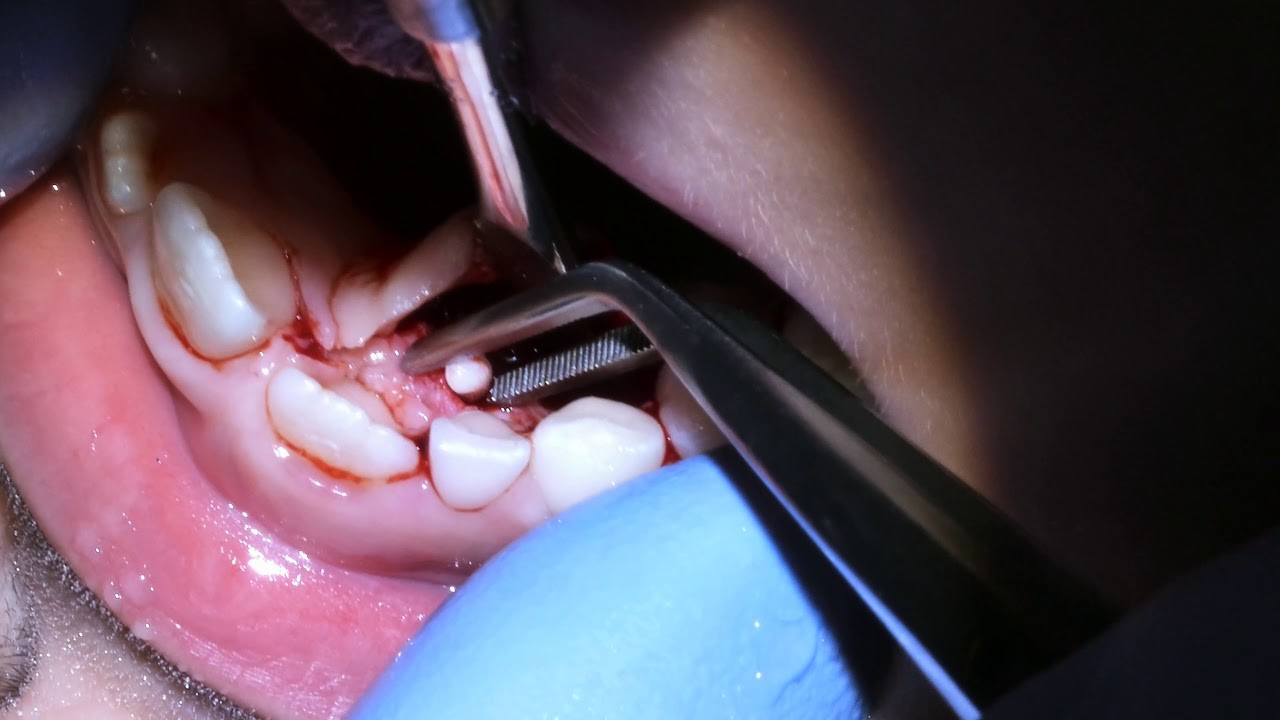

Removal

Removal surgery has been the tried-and-true treatment plan for odontomas — especially if they are causing any pain or affecting your teeth to erupt unnaturally. Some other things to know about odontoma removal surgery:

An oral or maxillofacial surgeon should consult your dentist on the surgery

The unerupted tooth associated with odontoma could be extracted if it's not developing correctly

If you have a tooth that needs extraction, discuss tooth replacement options and alignment issues with your dentist and/or orthodontist

Your dentist will likely recommend a combination of the following after surgery to help you heal: Proper oral hygiene, Cold and soft meals, No physical exercise for the first 48 hours, Pain relief medication, Antibiotic medication (if an infection is a concern).

Going through surgery is most likely your path should you be stricken with odontomas. But, it sure beats radiation or chemotherapy you'd have to face with cancer. Plus, the surgery to remove your odontomas is very common with few complications. Just remember to see your dentist regularly so they can identify the odontomas as early as possible on your X-rays.